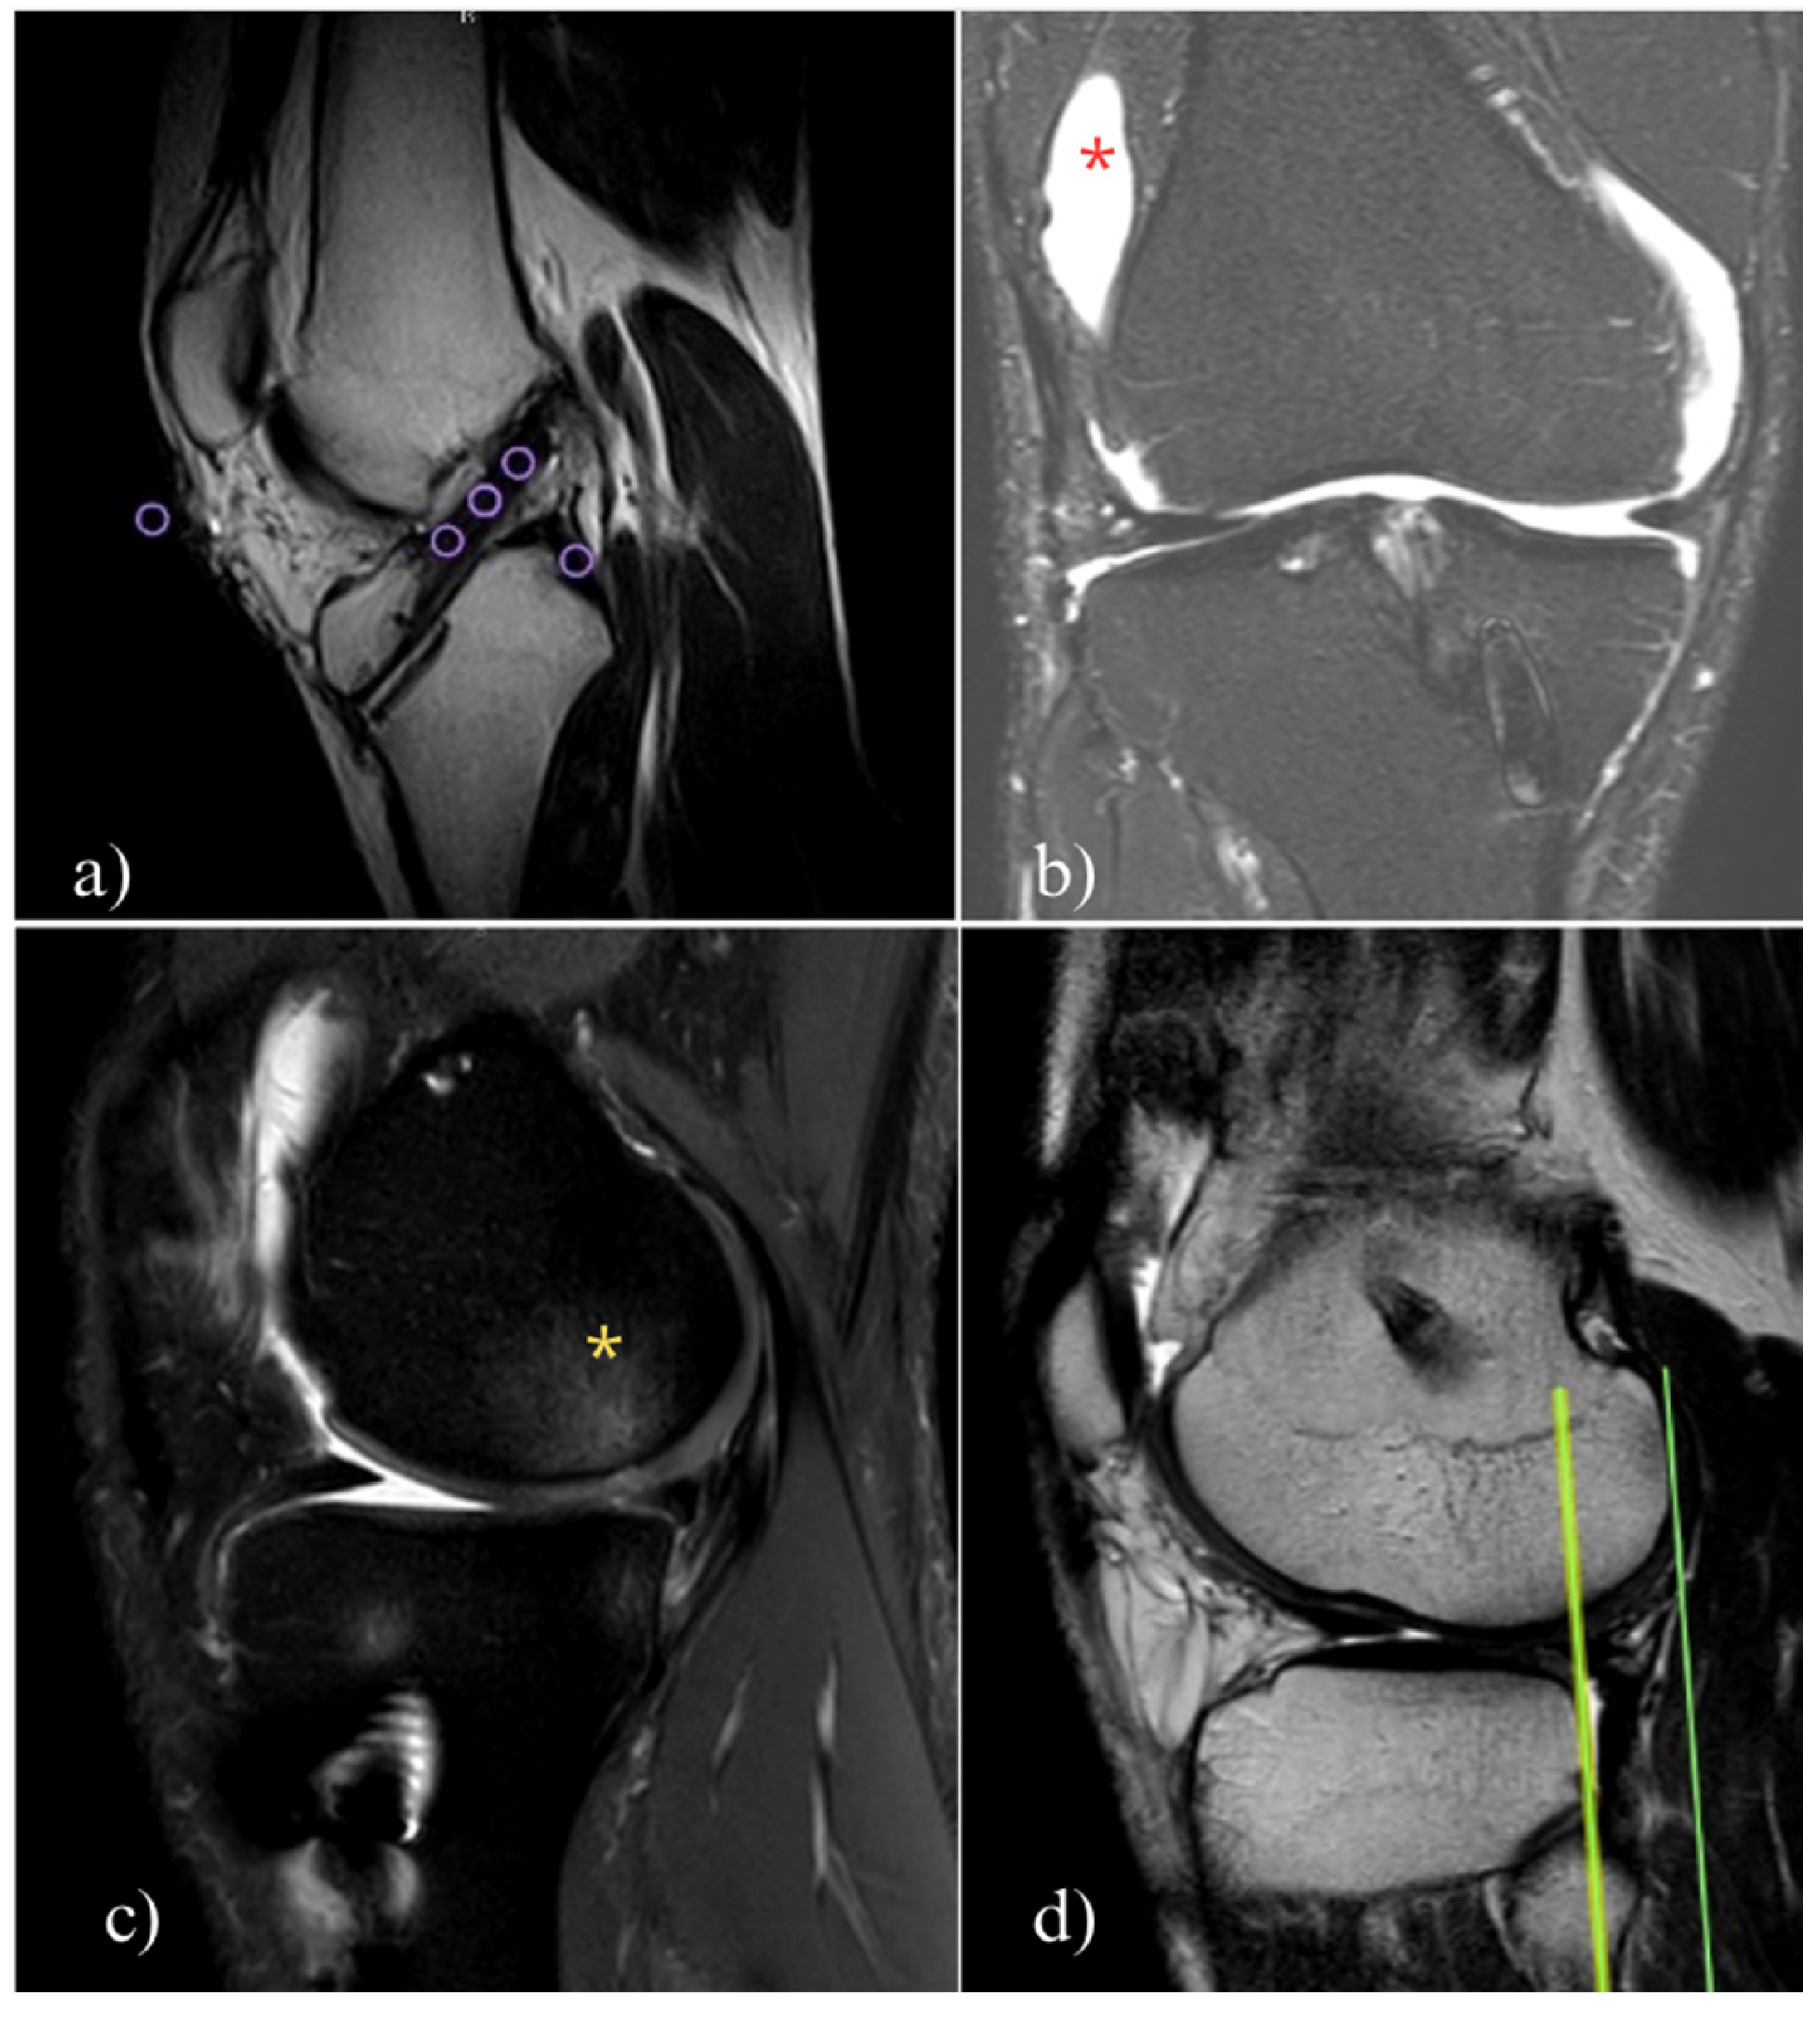

- Zdanowicz, U.; Ciszkowska-Łysoń, B.; Paśnik, M.; Drwięga, M.; Ratajczak, K.; Fulawka, K.; Lee, Y.C.; Śmigielski, R. Evaluation of ACL Graft Remodeling and Prediction of Graft Insufficiency in Sequenced MRI—Two-Year Follow-Up. Appl. Sci. 2021, 11, 5278. [Google Scholar] [CrossRef]

- DeFroda, S.F.; ODonnell, R.M.; Fadale, P.D.; Owens, B.D.; Fleming, B.C. The role of magnetic resonance imaging in evaluating postoperative ACL reconstruction healing and graft mechanical properties: A new criterion for return to play? Physician Sportsmed. 2021, 49, 123–129. [Google Scholar]

- Malahias, M.-A.; Capece, F.M.; Ballarati, C.; Viganò, M.; Marano, M.; Hofbauer, M.; Togninalli, D.; de Girolamo, L.; Denti, M. Sufficient MRI graft structural integrity at 9 months after anterior cruciate ligament reconstruction with hamstring tendon autograft. Knee Surg. Sports Traumatol. Arthrosc. 2022, 30, 1893–1900. [Google Scholar] [PubMed]

- Li, H.; Chen, J.; Li, H.; Wu, Z.; Chen, S. MRI-based ACL graft maturity does not predict clinical and functional outcomes during the first year after ACL reconstruction. Knee Surg. Sports Traumatol. Arthrosc. 2017, 25, 3171–3178. [Google Scholar]

- Zhou, T.; Xu, Y.; Zhang, A.; Zhang, X.; Deng, K.; Wu, H.; Xu, W. Association of Graft Maturity on MRI With Return to Sports at 9 Months After Primary Single-Bundle ACL Reconstruction with Autologous Hamstring Graft. Orthop. J. Sports Med. 2024, 12, 23259671241248202. [Google Scholar] [PubMed]

- Ma, Y.; Murawski, C.D.; Rahnemai-Azar, A.A.; Maldjian, C.; Lynch, A.D.; Fu, F.H. Graft maturity of the reconstructed anterior cruciate ligament 6 months postoperatively: A magnetic resonance imaging evaluation of quadriceps tendon with bone block and hamstring tendon autografts. Knee Surg. Sports Traumatol. Arthrosc. 2015, 23, 661–668. [Google Scholar] [PubMed]

- Biercevicz, A.M.; Akelman, M.R.; Fadale, P.D.; Hulstyn, M.J.; Shalvoy, R.M.; Badger, G.J.; Tung, G.A.; Oksendahl, H.L.; Fleming, B.C. MRI volume and signal intensity of ACL graft predict clinical, functional, and patient-oriented outcome measures after ACL reconstruction. Am. J. Sports Med. 2015, 43, 693–699. [Google Scholar]

- Hofbauer, M.; Soldati, F.; Szomolanyi, P.; Trattnig, S.; Bartolucci, F.; Fu, F.; Denti, M. Hamstring tendon autografts do not show complete graft maturity 6 months postoperatively after anterior cruciate ligament reconstruction. Knee Surg. Sports Traumatol. Arthrosc. 2019, 27, 130–136. [Google Scholar]

- Li, H.; Chen, S.; Tao, H.; Li, H.; Chen, S. Correlation analysis of potential factors influencing graft maturity after anterior cruciate ligament reconstruction. Orthop. J. Sports Med. 2014, 2, 2325967114553552. [Google Scholar]

- Van Dyck, P.; Clockaerts, S.; Wouters, K. MRI signal intensity changes in ACL grafts: Clinical significance and implications for return to sport. Eur. Radiol. 2021, 31, 4102–4113. [Google Scholar]